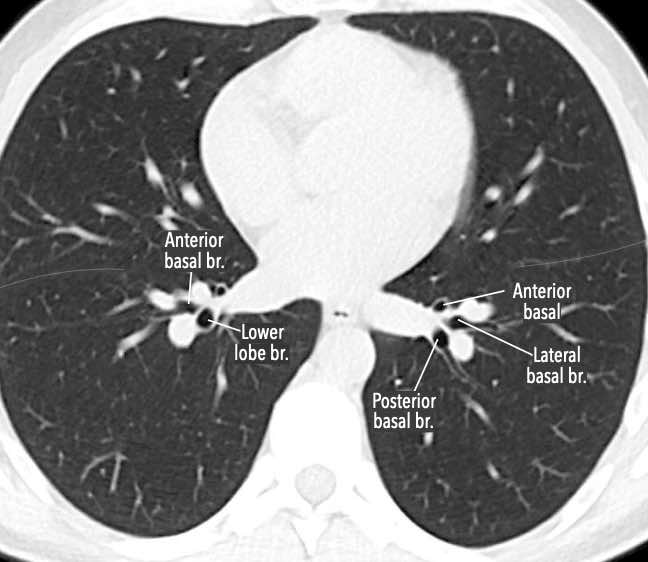

Phế quản trên CT

Cuộn qua các hình ảnh để quan sát khí quản phân chia thành phế quản chính phải và trái, sau đó tiếp tục phân chia thành các phế quản thùy và phế quản phân thùy.